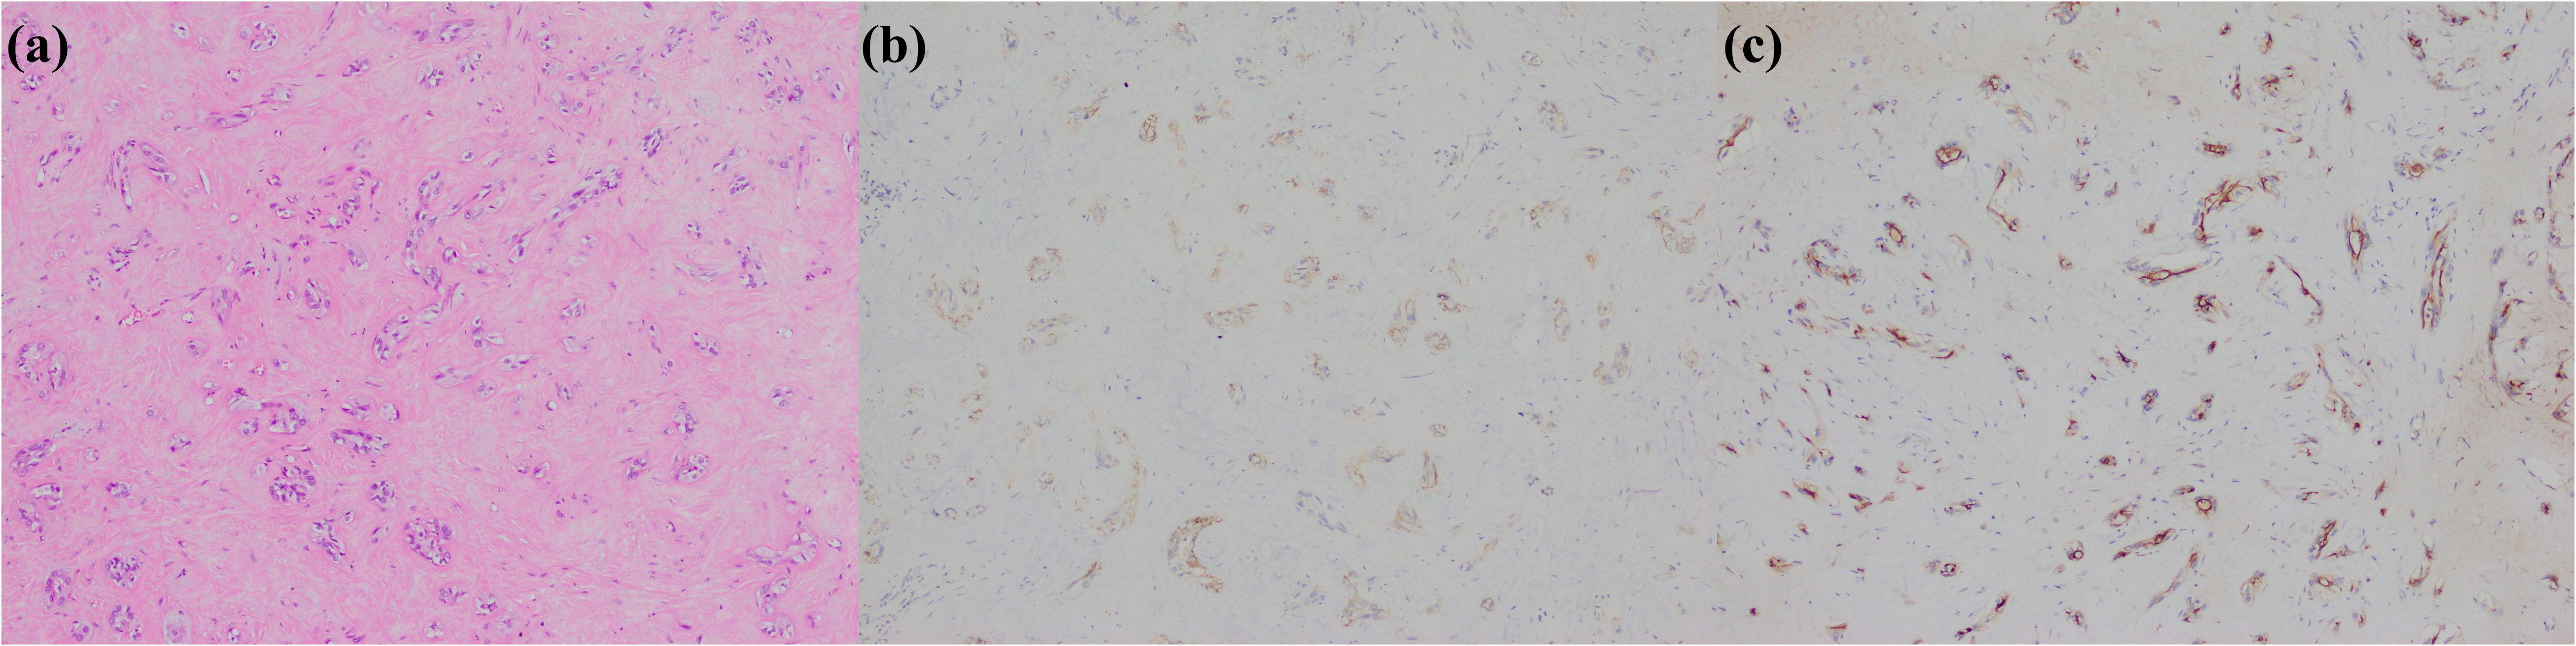

In summary, the immunohistochemical markers of large duct type iCCA are frequently expressed in the cytoplasm of tumor cells and are closely associated with secreted mucus (Figure 1). Consequently, numerous studies utilized Alcian Blue staining or Alcian Blue-Periodic Acid-Schiff staining to differentiate subtypes of iCCA. Positive staining is indicative of large duct type iCCA (percentage of positive cases of mucus staining in large duct type iCCA vs. small duct type iCCA: 82.0%~100% vs. 10.7%~45%) (18, 19, 21, 23, 52, 59, 68). However, since adenocarcinomas from other organs can produce similar mucus and metastasize to the liver, these markers are primarily used to distinguish large duct type iCCA from small duct type iCCA and should be cautiously employed when differentiating large duct type iCCA from other liver-metastatic adenocarcinomas. Organ-specific markers for large duct type iCCA remain undefined. Due to the same embryonic origins, adenocarcinomas arising from the pancreas, ampulla, stomach, extrahepatic bile ducts, and gallbladder exhibit highly similar immunohistochemical profiles to large duct type iCCA. In such cases, histological evidence of premalignant lesions is essential, such as biliary intraepithelial neoplasia or intraductal papillary neoplasms of the bile ducts. Furthermore, large duct type iCCA typically demonstrates abundant fibrous stroma and dilated mucin-rich tumor glands compared to metastatic adenocarcinomas to the liver, though this is not absolute. Additionally, imaging findings and clinical information should be emphasized. Metastatic adenocarcinomas often manifest as multiple subcapsular lesions accompanied by tumors in other organs and corresponding clinical symptoms, whereas large duct type iCCA predominantly shows infiltrative growth along the intrahepatic bile ducts near the porta hepatis. When the diagnosis is uncertain despite these considerations, pathological reports should employ cautious terminology and recommend multidisciplinary treatment. Given the significant differences in treatment, organ-specific immunohistochemical markers for adenocarcinomas originating from the upper gastrointestinal tract, large bile ducts, and pancreas are critically needed.

Figure 1. Large duct type iCCA. (a) histological morphology; (b) S100P positive; (c) MUC5AC positive; (d) MUC6 positive (magnification: 100×).